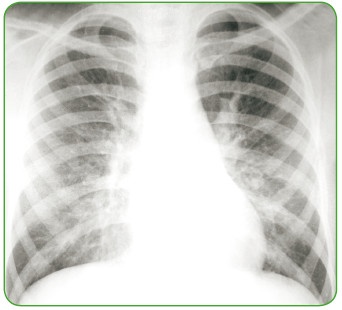

Иллюстрация к книге — Энциклопедия диагностики и лечения от А до Я [i_204.jpg]

Рентгенограмма грудной клетки